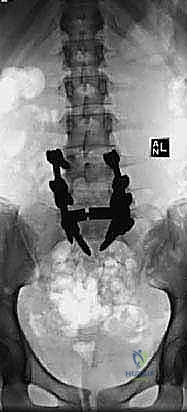

- الأشعة السينية الديناميكية (Dynamic X-rays): صور في وضعية الانحناء للأمام والخلف لتقييم مدى عدم استقرار الفقرات وحركتها غير الطبيعية.

- التصوير المقطعي المحوسب (CT Scan): يقدم تفاصيل دقيقة للبنية العظمية، وهو ضروري جداً للتخطيط الجراحي وتحديد مسار المسامير (Pedicle Screws) في الجراحة.

2. الدمج الخلفي الجانبي (Posterolateral Fusion - PLF)

بعد تحرير الأعصاب، يجب تثبيت العمود الفقري. في تقنية الدمج الخلفي الجانبي، يتم وضع مسامير من التيتانيوم (Pedicle Screws) في جذور الفقرات، وتوصيلها بقضبان معدنية قوية. ثم يتم وضع طعوم عظمية (Bone Grafts) - تؤخذ عادة من عظام الحوض للمريض أو من بنك العظام - على الأجزاء الجانبية للفقرات (Transverse Processes). بمرور الأشهر، ينمو العظم الجديد ليلحم الفقرات معاً ككتلة عظمية واحدة صلبة، مما يمنع أي حركة غير طبيعية.